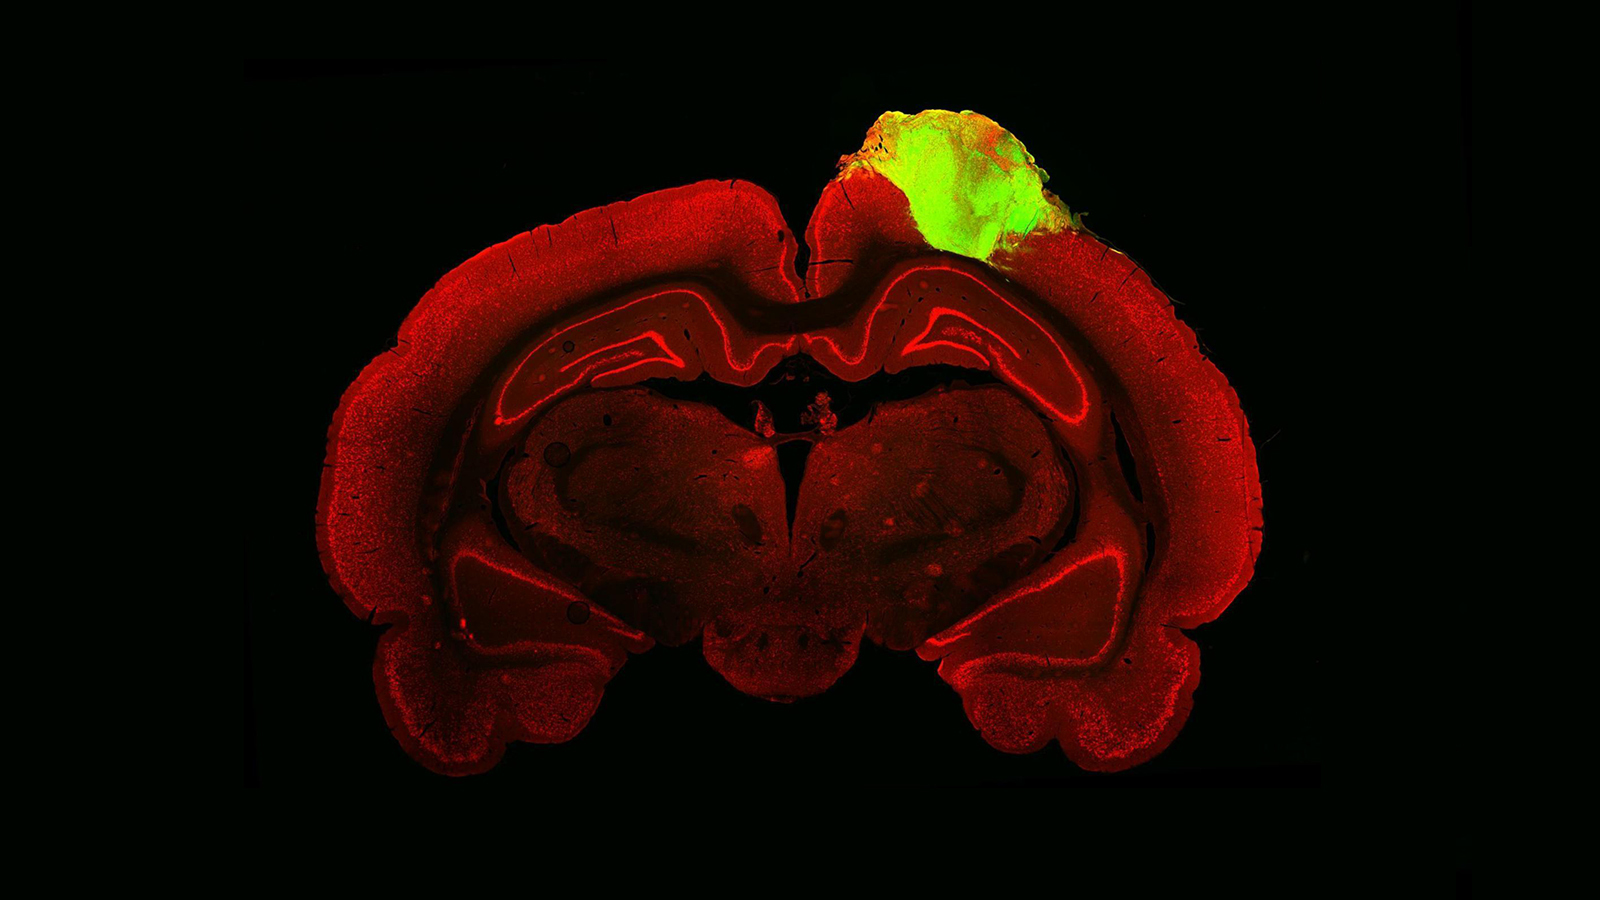

Researcher Silvya Maria-Engler and colleagues at the University of Sao Paulo first examined cross-sections of bioprinted epidermis under the microscope, and compared them with samples of real skin.

To simplify the task, they used fluorescent dyes which targeted specific biomolecules in the samples, allowing them to visualise their cellular structures more easily. In the colourful cross-sections, the researchers found that the artificial material exhibited all four of the key layers found in the real epidermis, each defined by their unique cellular architectures.